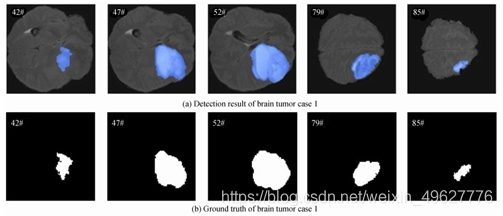

从脑肿瘤测试集中任选3个病例样本进行检测结果可视化分析,图 17~19分别为3个病例中5个序列的检测结果,以及对应序列的脑肿瘤病灶金标准图.

图 17 脑肿瘤病例1结果图

从图 17~19可以看出,设计的多模态脑肿瘤病灶检测方法所得到的检测结果,与金标准拟合程度高,说明该方法可有效检测出MRI脑部影像中脑肿瘤病灶.